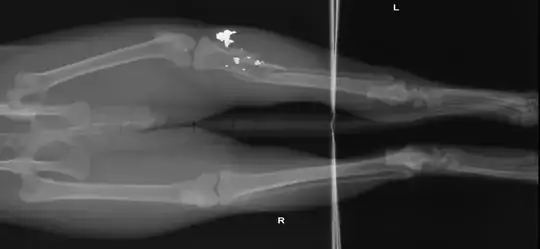

What are the white/opaque shards in these cat leg X-rays?

The entry wound is very small. Just a 1/2 inch cut on the inside of the leg. No cuts on the outside of the leg.

As @Harry V. suggested in a related post, the shards turned out to be lead pellet gun fragments.

In the left proximal tibia and fibula there are highly comminuted fractures and mild displacement, moderate soft tissue swelling and a large amount of metal debris at the fracture site.

The left hip is luxated and abnormal. The femoral head and neck are abnormally shaped and have moderate particular new bone formation on all aspects. Not other abnormalities are detected.

1. Comminuted mildly displaced proximal left tibial and fibula fractures tue to a projectile injury (gunshot of some type).

2. Luxated left hip with abnormal conformation and moderate osteoarthrosis. The chronic changes in this hip are likely due to avascular necrosis of the femoral head and neck and/or a proximal physeal fracture. Hip dysplasia cannot be completely ruled out; however it is less likely since there is normal conformation in the right hip.

I'm surprised that a pellet could shatter multiple bones like that. It must have been a very unlucky shot.